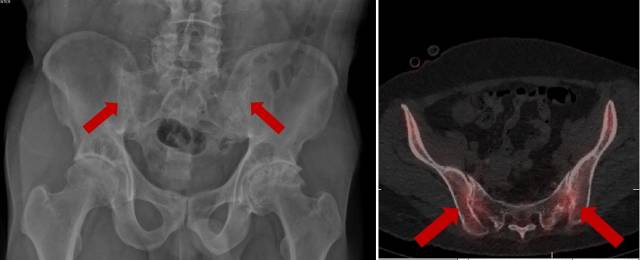

강직성 척추염 의심 증상이 나타나면 엑스레이 검사, 혈액검사 등을 시행해 진단할 수 있다. 최근에는 엑스레이 검사에서 관절 이상이 뚜렷하지 않은 초기 병변의 경우 천장골 중심 자기공명영상(MRI) 또는 뼈 스캔 검사 등이 진단에 많이 이용된다. 아직까지 강직성 척추염의 원인은 정확히 밝혀져 있지 않다. 유전적 요인이 관여하는것으로 알려져 있을 뿐이다. 대부분의 강직성 척추염 환자는 다른 사람에게 잘 나타나지 않는 항원(HLA-B27)이 나타난다. 항원을 가졌다고 반드시 강직성 척추염이 발생하는 것은 아니지만 그렇지 않은 사람들에 비해 발병 가능성이 크다. 미생물이나 소장 또는 대장에 발생하는 만성 염증도 강직성 척추염 발병과 연관되는 것으로 여겨진다.